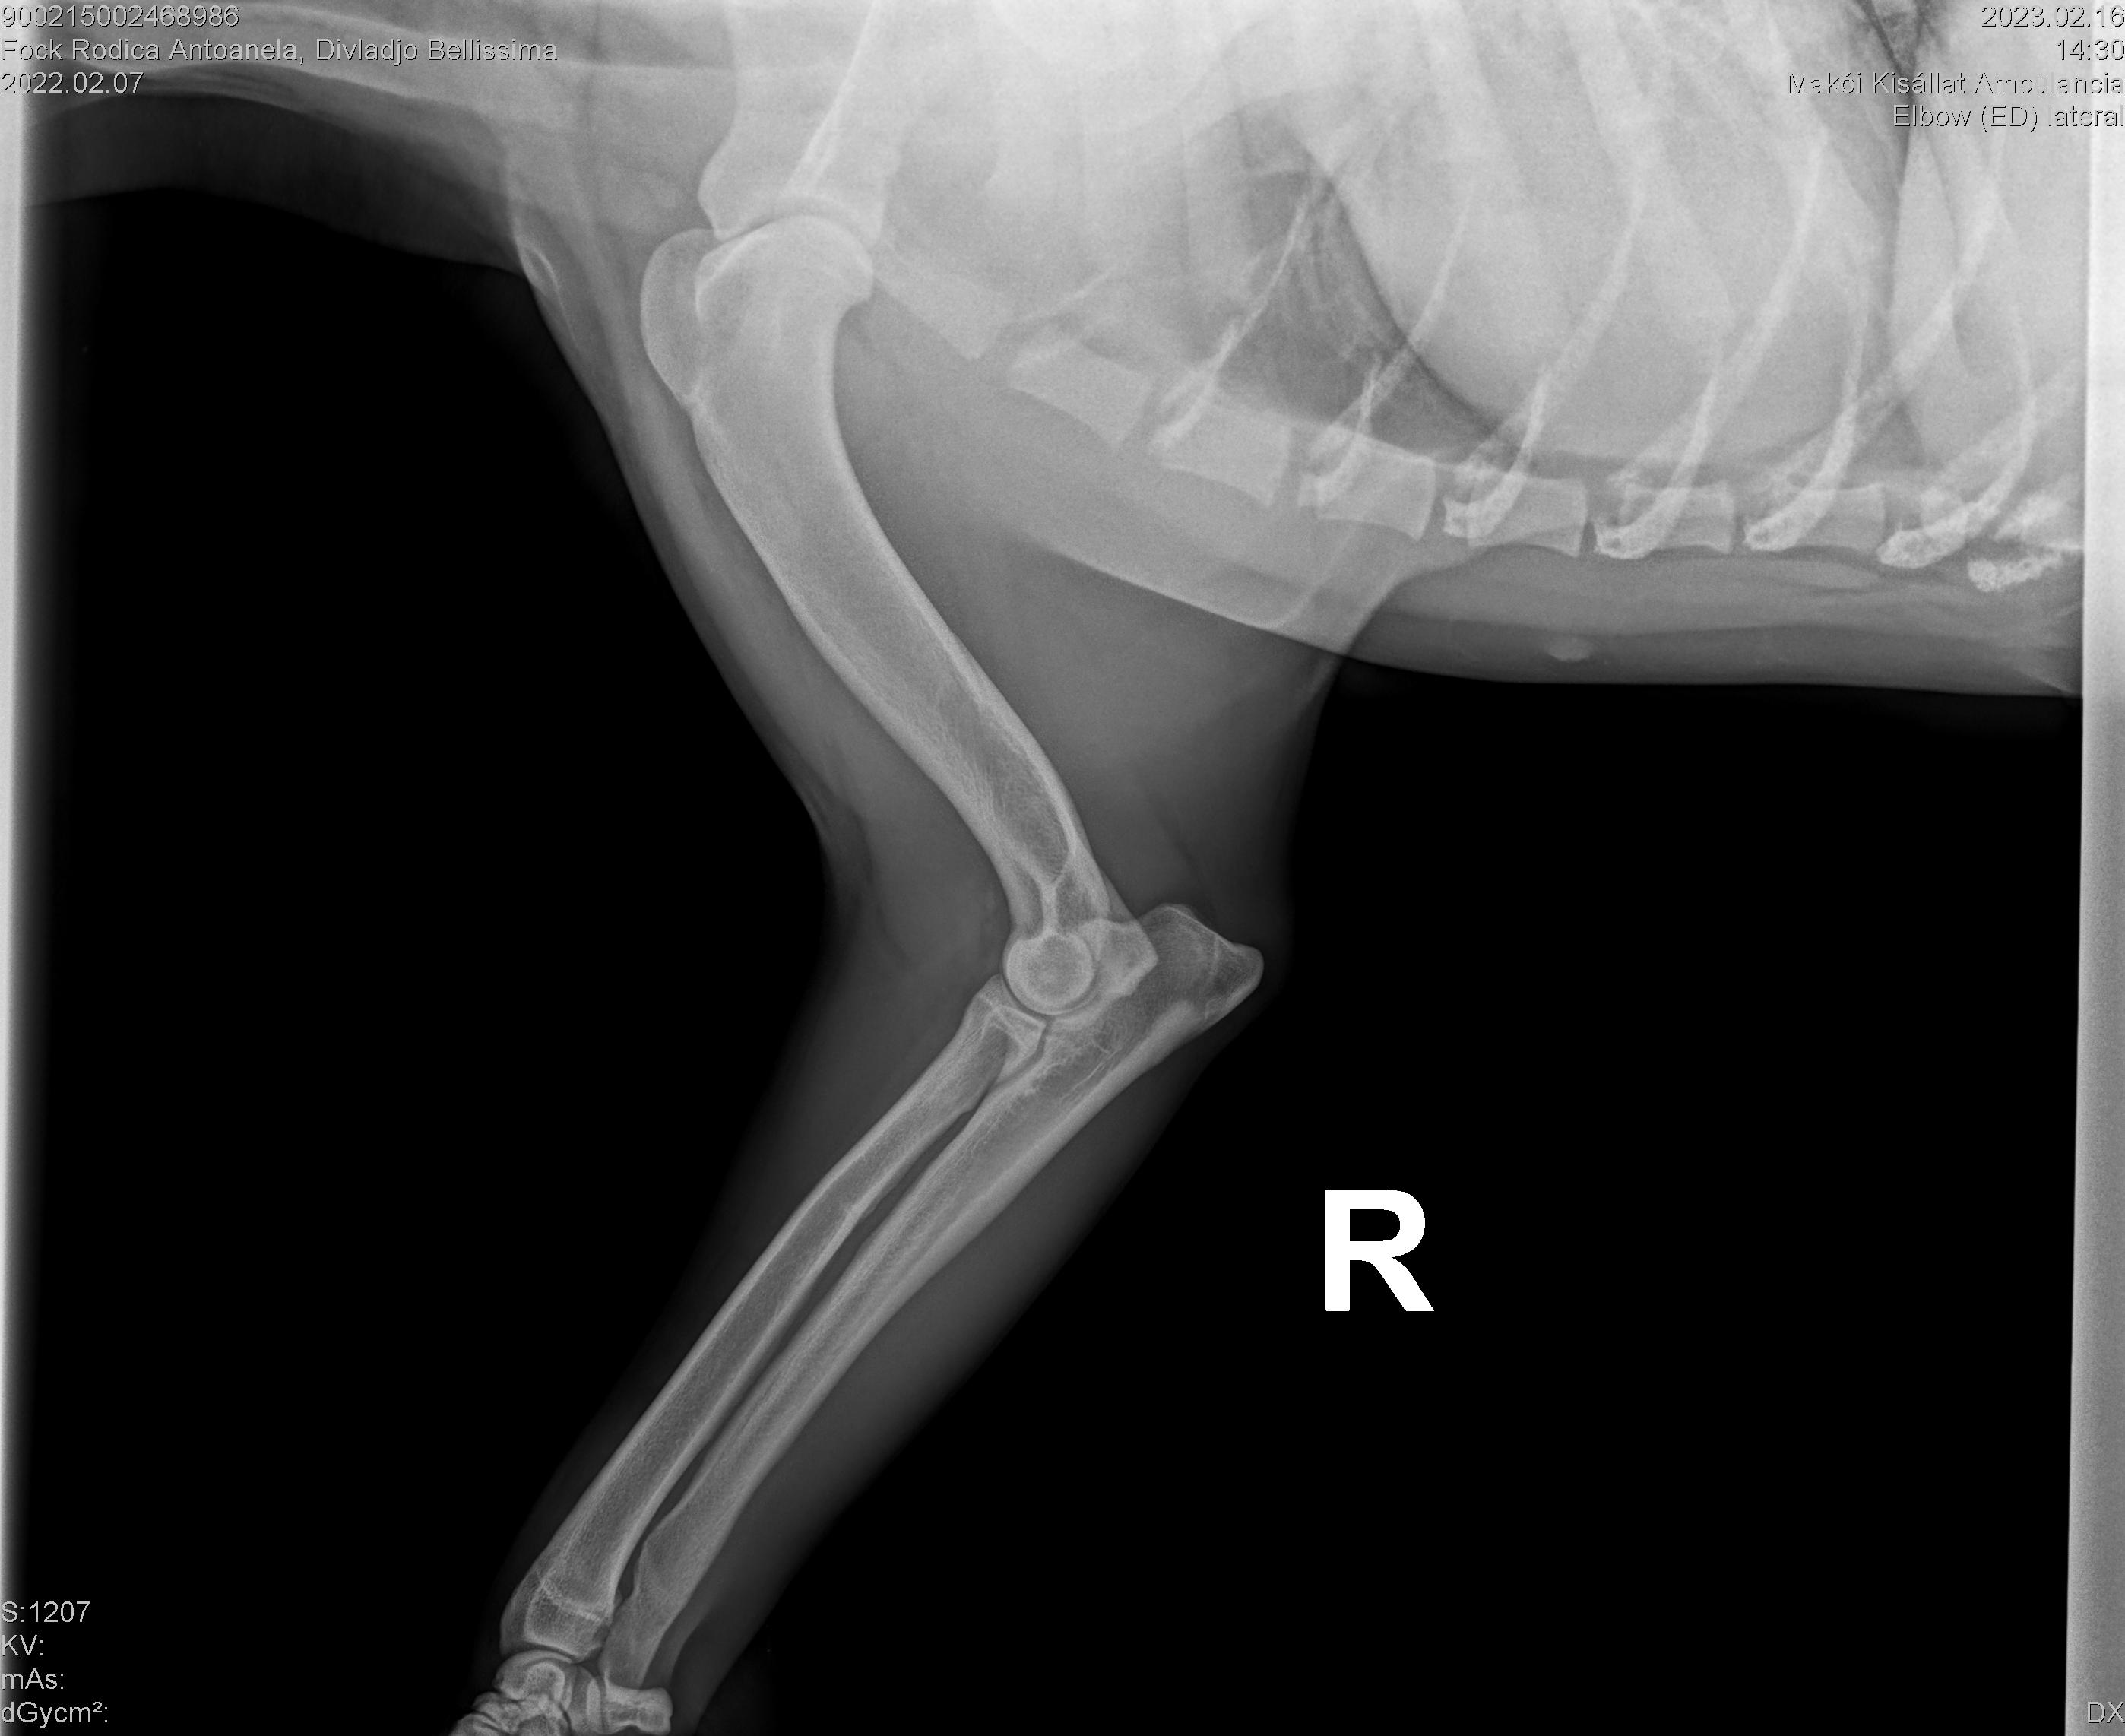

DIVLADJO BELLISSIMA

( BELLISSIMA )

Data nasterii:

07.02.2022